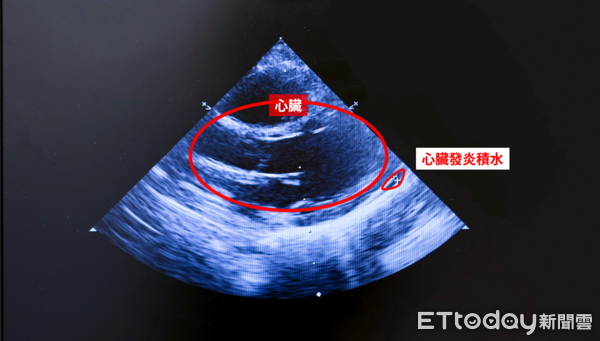

▲男童罹患川崎氏症,影像檢查發現心臟已發炎、積水。(圖/中醫大新竹附醫提供,下同)

一名1歲多男童高燒合併腹瀉,體溫超過39度,原以為是腸胃炎,用藥卻未緩解不適,仍反覆發燒,並出現眼睛發紅、紅疹,及嘴唇紅腫、乾裂等症狀,經抽血與心臟超音波檢查,確診為川崎氏症,經免疫球蛋白治療後,症狀終於改善。

曾思穎也說,該男童確診後,接受靜脈注射免疫球蛋白治療,體溫迅速降回正常,症狀明顯改善;此症患者若未及時治療,約25%可能出現冠狀動脈擴張或動脈瘤,甚至影響心臟功能,故需在發燒10天內完成診斷並給予免疫球蛋白治療。